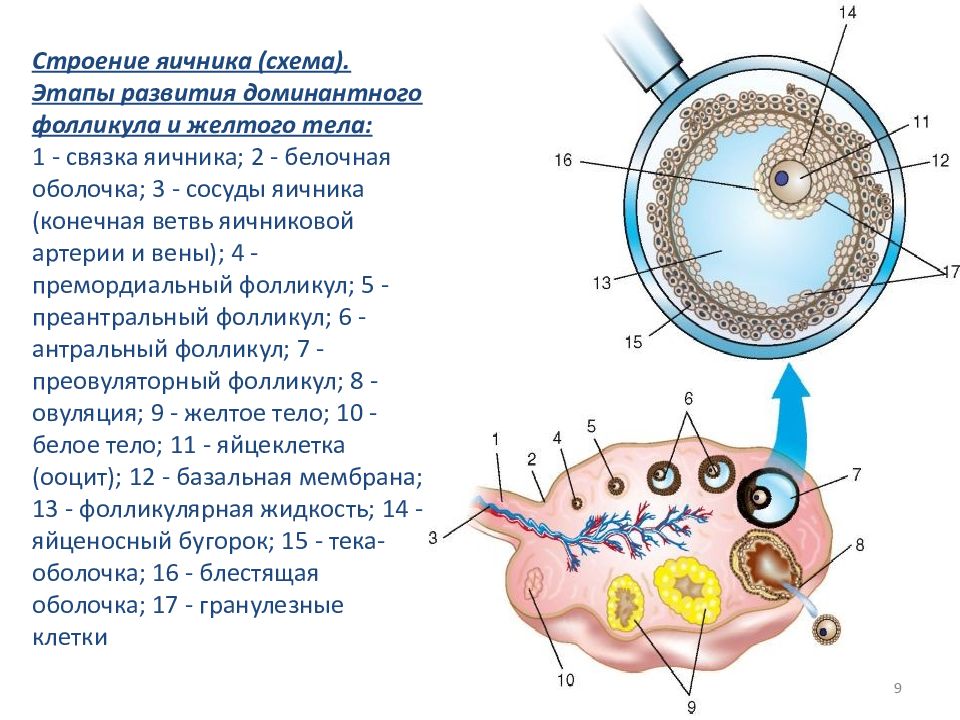

Созревание фолликула в яичнике: этапы и процессы

Раздел: Другие животные